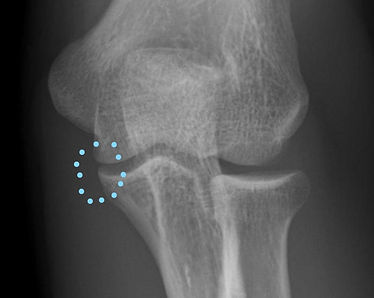

成人例

29歳男性、小児期から野球を本格的に行っていました。

数年前から投球時に痛みが出ていましたが我慢しながら投球していました。

右肘X線 尺骨内側に骨棘ができています。